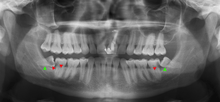

Wisdom teeth likely become impacted because of a mismatch between the size of the teeth and the size of the jaw. Impacted wisdom teeth are classified by their direction of impaction, their depth compared to the biting surface of adjacent teeth and the amount of the tooth's crown that extends through gum tissue or bone. Impacted wisdom teeth can also be classified by the presence or absence of symptoms and disease. Screening for the presence of wisdom teeth often begins in late adolescence when a partially developed tooth may become impacted. Screening commonly includes clinical examination as well as x-rays such as panoramic radiographs.

If the tooth cannot be assessed with clinical exam alone, the diagnosis is made using either a panoramic radiograph or cone-beam CT. Where unerupted wisdom teeth still have eruption potential several predictors are used to determine the chance of the teeth becoming impacted. The ratio of space between the tooth crown length and the amount of space available, the angle of the teeth compared to the other teeth are the two most commonly used predictors, with the space ratio being the most accurate. Despite the capacity for movement into early adulthood, the likelihood that the tooth will become impacted can be predicted when the ratio of space available to the length of the crown of the tooth is under 1.[3]:141

There is no standard to screen for wisdom teeth. It has been suggested, absent evidence to support routinely retaining or removing wisdom teeth, that evaluation with panoramic radiograph, starting between the ages of 16 and 25 be completed every 3 years. Once there is the possibility of the teeth developing disease, then a discussion about the operative risks versus long-term risk of retention with an oral and maxillofacial surgeon or other clinician trained to evaluate wisdom teeth is recommended. These recommendations are based on expert opinion level evidence.[17] Screening at a younger age may be required if the second molars (the "12-year molars") fail to erupt as ectopic positioning of the wisdom teeth can prevent their eruption. Radiographs can be avoided if the majority of the tooth is visible in the mouth.